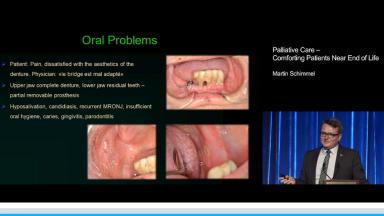

Palliative Care – Comforting Patients Near End of Life

This presentation discusses dental treatment in patients considered to be near the end of life. Comfort care and palliative treatment may be the only options for this category of patients. This lecture advocates forward thinking during treatment planning and a multidisciplinary approach due to the complex interactions of oral health. The effects of palliative care on the mouth in the form of xerostomia, oral pain, and discomfort are emphasized. The lecturer also presents considerations for dental implants during palliative care, including indications for removing superstructures.

- comprehend the oral problems in palliative patients

- list oral manifestations that appear in near end-of-life patients